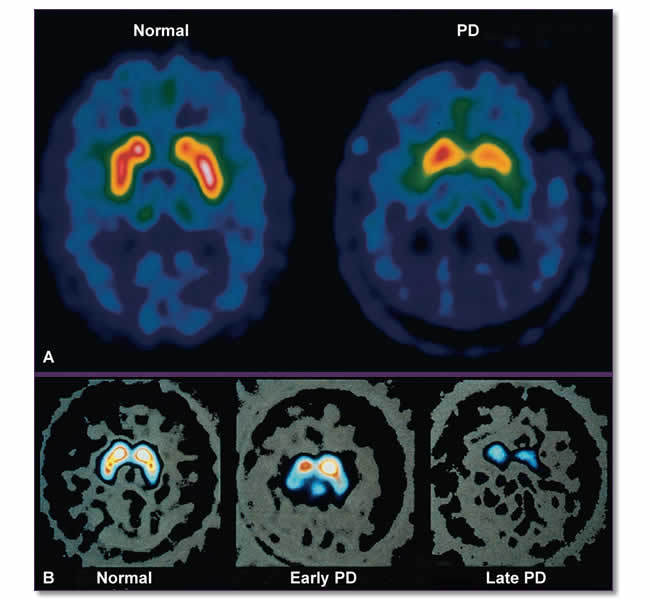

파킨슨병 운동치료 : 미소들병원 / Jun 04, 2021 · 운동을 조절하는 뇌 부위에서 분비되는 신경전달물질 도파민 생산 세포가 소실되면서 근육 경직, 몸 떨림, 느린 동작 같은 운동장애가 나타나는 ‘파킨슨병.

Jun 16, 2021 · wire hanging test는 파킨슨병 같은 퇴행성뇌질환에서 운동신경 손상, 회복을 평가하는 검사 파킨슨병 실험적 모델 연구: We would like to show you a description here but the site won't allow us. Feb 22, 2021 · 환각은 파킨슨병 치료에 사용되는 약에 의해서도 생길 수 있고, 파킨슨병 자체에 의해서도 생길 수도 있다. 종합건강검진, 국민건강보험공단검진, mri, ct, 특수건강검진, 채용신체검사, 인터넷검진 예약 May 31, 2021 · 코아스템166480은 파킨슨병 치료용 줄기세포 개발을 위해 한양대학교 산학협력단과 기술이전 계약을 체결했다고 31일 밝혔다. 15 우울증 의 빈도도 크게 증가한다. 환시, 치매, 우울증과 같은 비운동증상이 발생한 환자들은 그렇지 않은 환자들에 비해서 진행이 빠르고 더 증상이. 신경전달물질 도파민 생산 세포가 소실되면서 근육 경직, 몸 떨림, 느린 동작 같은 운동장애가 나타난다.